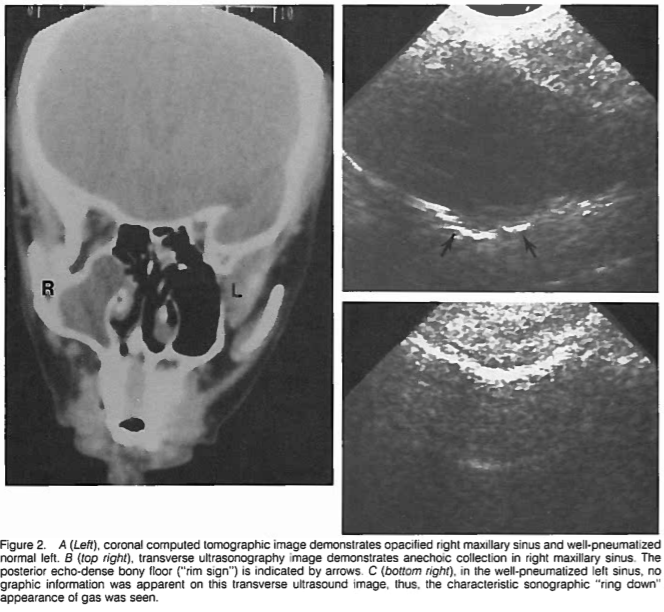

좌측그림: 비대된 점막의 우측 부비동, 우측그림: 물이 찬 좌측 부비동

부비동염 (축농증)에서는

부비동의 경계선이 보일 수 있고

점막의 비대나

새까맣게 물이 찬 것이 보입니다.

물이 찬 부비동의 CT / US image